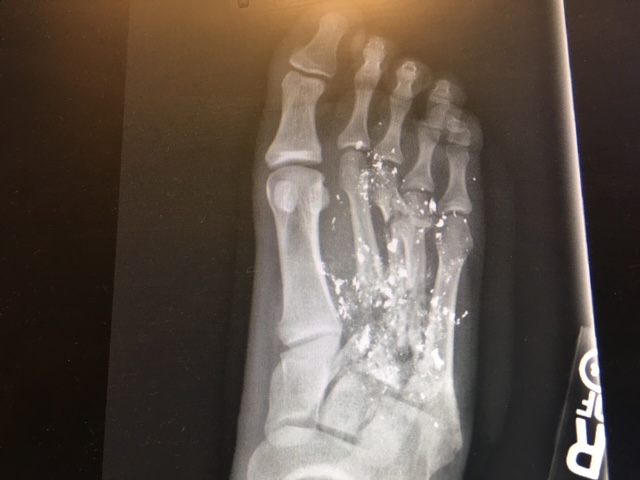

Is Radiology Boring? Gallery Is Radiology Boring? By Nicole Angemi|2025-08-28T11:51:17-04:00July 31st, 2022|The Gross Room, FREAK ACCIDENT, Gunshot Wound, TRUE CRIME| Read More 26